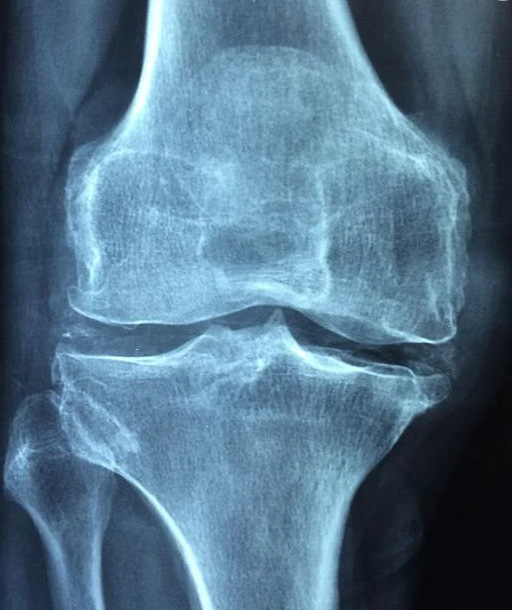

관절염이라고 하면 대부분이 골관절염에 해당이 됩니다. 관절을 보호하는 연골이 마모되면 뼈를 보호해주는 보호막이 없어지기 때문에 통증이 나타나며, 이차적인 손상 으로 이어지면 뼈에 변형까지 나타날 수 있는 질병입니다.

골관절염은 관절을 많이 사용하거나 사용하고나면 통증이 나타나고, 쉬면 통증이 가라앉는 특징을 가집니다. 심한 통증의 경우 관절 주위를 누르기만 해도 통증이 있습니다. 골관절염이 많이 진행되면 관절 변형도 발생하여 관절의 가동범위가 좁아지게 됩니다.